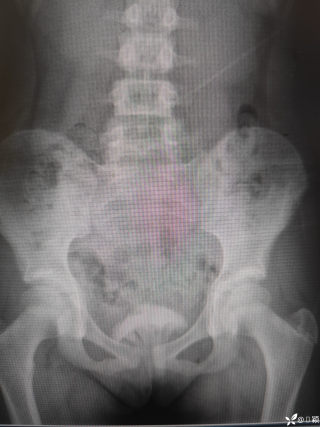

灼见|如果是你,如何处置山东男孩(多器官切除病例)

文/西地兰 特别声明:所有观点仅代表个人言论 特别声明:与当事双方均无利益相关 山东男孩,目前全网沸沸扬扬,看过一些观点,直言不讳地说,大多偏颇。要么一股脑地指责医方的全责,甚至有说千万别在县医院看病。要么又为医方无休止的遮羞,认为这样的手术在县医院做下来已经非常了不起。而我想到的是,以后面临类似的病例,我们怎么办?那么我们不如来一次专业的病案讨论。既然是事后讨论,难免有事后诸葛亮的感觉,但是假如下一次,同行们遭遇这样的病例,如何处置?这是医疗行业所面临的问题。希望我整理的这些思路和相关病例,对同行们有所帮助!就目前的资讯外界不足以判断是否需要急诊,如果需要急诊,那么只能根据术中所见进行处理,

2023年10月26日,来自山东菏泽市成武县的小烨和他家人的命运被彻底改变了。这个原本阳光、可爱的小男孩在一次意外被撞击后,在医院检查出了腹腔内存在肿瘤,并在手术中被切除了包括十二指肠、胰腺、大部分胃和小肠等多个器官。此后便无法再像正常人一样吃饭、喝水,活着要靠长期静脉注射营养液。一份2024年12月由第三方机构出具的司法鉴定意见书显示,当时给小烨做手术的成武县人民医院在该医疗行为中存在过错,与小烨的损害后果之间存在因果关系,建议医疗过错在损害后果中的原因力大小为同等原因。此外,另一份由成武县卫生健康局在2025年9月28日发出的书面答复中显示,成武县人民医院存在24小时内未完成病历;手术知情